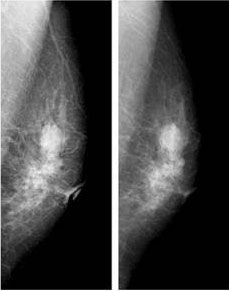

PCM 圖像(左)和傳統 SF 圖像(右)

圖7 為臨床圖像實例(圖片來自滋賀醫科大學)。兩圖分別為同一被攝個體的 PCM 圖像(左)和傳統 SF 圖像(右),兩次放射劑量相同,相比可見 PCM 圖像顯示的乳腺組織更為清晰。在對多幅臨床圖像進行分析后,現已證實 PCM 系統在顯現微小鈣化圖像方面優于傳統 SF 成像系統,而識別微小鈣化正是乳腺X線攝影的主要任務。

圖7 不同乳腺X線的攝影效果